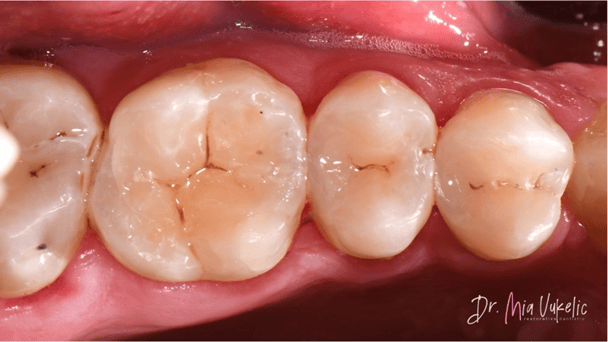

Como puede observarse en las imágenes finales, la resina Transcend™ ofrece una apariencia estética excepcional para la restauración. El sistema de matrices seccionales Halo permitió lograr una excelente anatomía proximal, tal como se aprecia en la radiografía.

Lograr una mimetización invisible en el sector posterior sigue siendo uno de los mayores retos en la odontología restauradora. En este caso, la combinación de la técnica centrípeta y las propiedades ópticas de Transcend facilitaron un acabado donde la línea de unión es imperceptible.